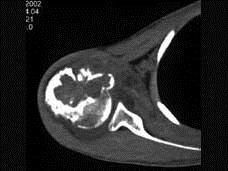

问题 男,29岁,右肩肿物4年,质地硬,压痛不明显,请结合图像,选择最佳答案 ( )

选项 A、巨细胞瘤 B、软骨肉瘤 C、骨转移瘤 D、成软骨细胞瘤 E、结核

答案 D